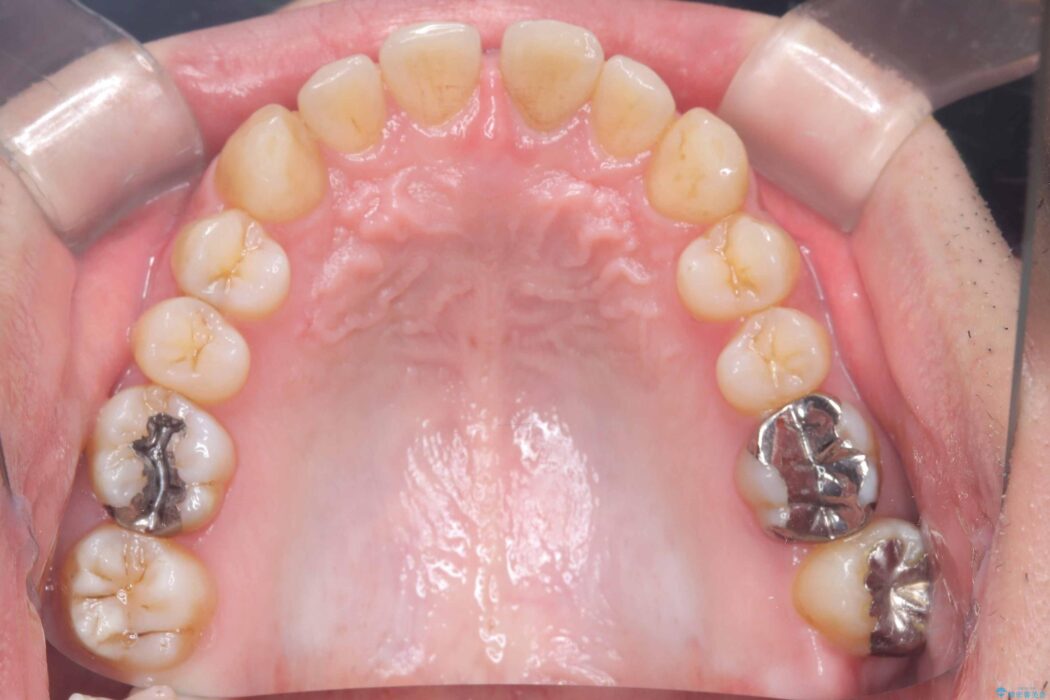

前歯の隙間とガタつきが気になるとご来院された患者様です。

正中離開・叢生のほかに、上下の奥歯が全く咬み合わないシザーズバイトの状態も認められました。